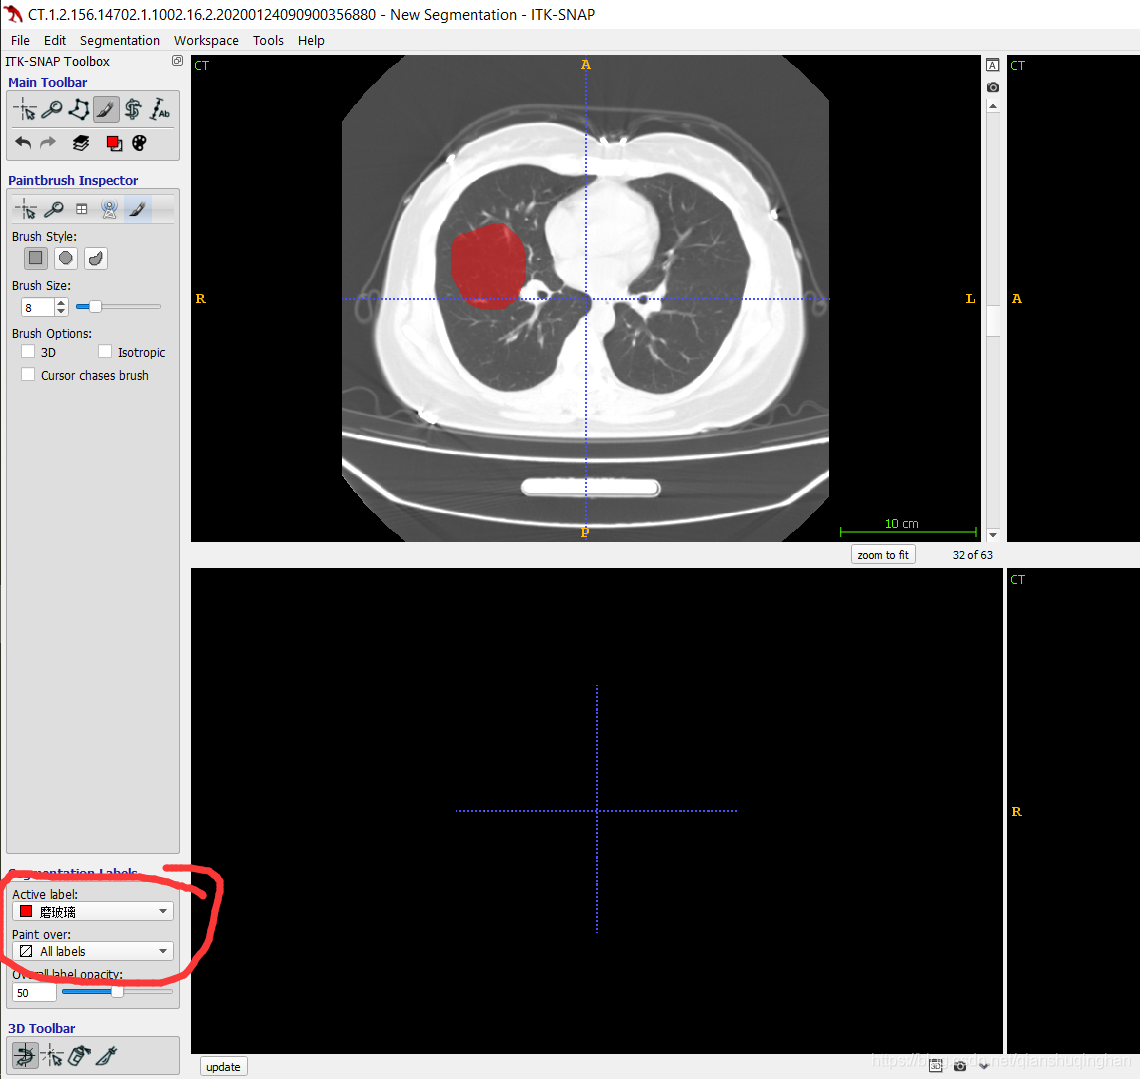

勾画对应病灶前,记得先选择病灶的类型label(软件左下角):Active Label

调整病灶的标签(比如,从磨玻璃 调整为实变)

如想将此标签从当前的磨玻璃改成实变,选择画刷模式,将Active label选为实变,将paint over选为磨玻璃,然后用笔刷涂抹即可修改

调整完后,切记将Active label选为你需要画的类型,将paint over恢复All labels